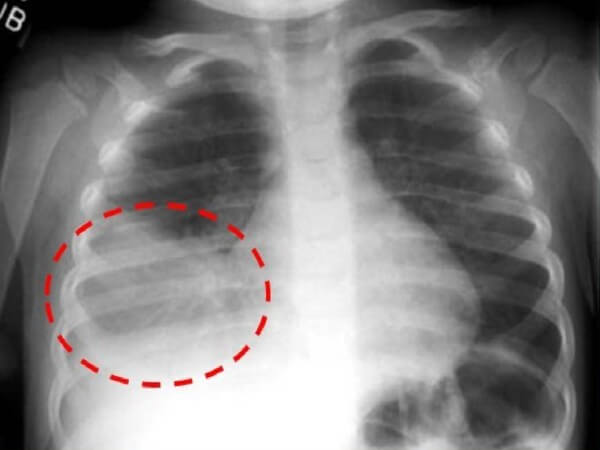

Нижнедолевая правосторонняя пневмония

Диагностика

Диагностика правосторонней пневмонии основывается на клинической картине, аускультативных и лабораторных симптомах.

К необходимым обследованиям при подозрении на воспаление лёгких относят:

- осмотр врача-педиатра;

- рентгенография органов грудной клетки в прямой и боковой проекциях;

- общий анализ крови;

- микроскопия мокроты, её бактериологический анализ для определения чувствительности возбудителя к антимикробным препаратам.

К критериям для постановки диагноза относят:

- лихорадку выше 38°C;

- кашель с выделением гнойной мокроты;

- лейкоцитоз в общем анализе крови;

- физикальные и аускультативные симптомы (укорочение перкуторного звука, крупно- и среднепузырчатые хрипы над областью поражения)

Особенности диагностики

Процесс воспаления верхней правой легочной доли отлично просматривается на рентгене. Однако пациенту с внебольничной правосторонней верхнедолевой пневмонией все же нужно пройти как инструментальное, так и лабораторное и клиническое обследование:

- Обследование клиническое. Специалист-пульмонолог либо терапевт во время внешнего осмотра увидит бледность кожи, в младшей возрастной группе – синеватый оттенок носогубного треугольника. Прослушивание позволяет обнаружить на верхушке легкого крепитацию, жесткое и ослабленное дыхание, хрипы.

- Рентген. Рентгенография осуществляется в двух проекциях. Обнаруживается на рентгенограмме затемнение верхней доли, а также усиление рисунка легкого.